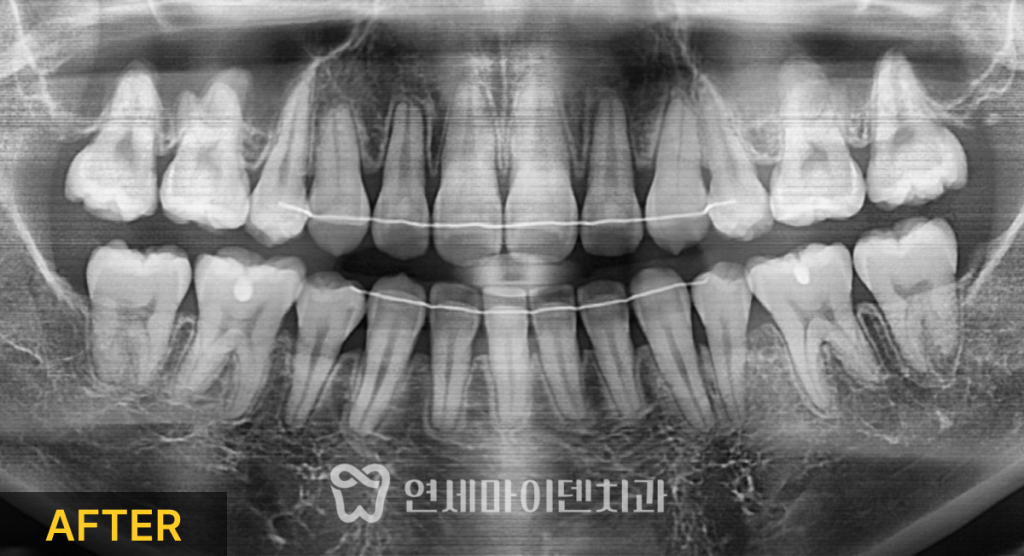

치료 완료 및 결과 분석

약 23개월의 교정 치료 후,

앞니 개방교합은 완전히 닫혔고

치아 배열도 가지런하게 정리되었습니다.

좌우 중심선이 맞춰졌고,

어금니 교합 역시 고르게 맞물리도록 조정되었습니다.

전체 치열은 안정적인 U자형으로 형성되었습니다.

치료 전후 중첩 분석 결과,

발치를 통해 앞니는 안쪽으로 이동했고

어금니를 위로 함입하면서

아래턱이 위쪽으로 회전한 것이 확인되었습니다.

그 결과

입술 돌출이 줄어들고

턱 끝 아래쪽에는 자연스러운 S라인이 형성되며

안모 또한 조화롭게 개선되었습니다.

파노라마 방사선 사진에서도

치아 뿌리 방향은 치료 전과 유사하게 유지되었고,

치근 흡수 역시 기능에 문제되지 않을 정도로

안정적으로 마무리되었습니다.

발치 공간도 모두 완전히 닫힌 상태였습니다.